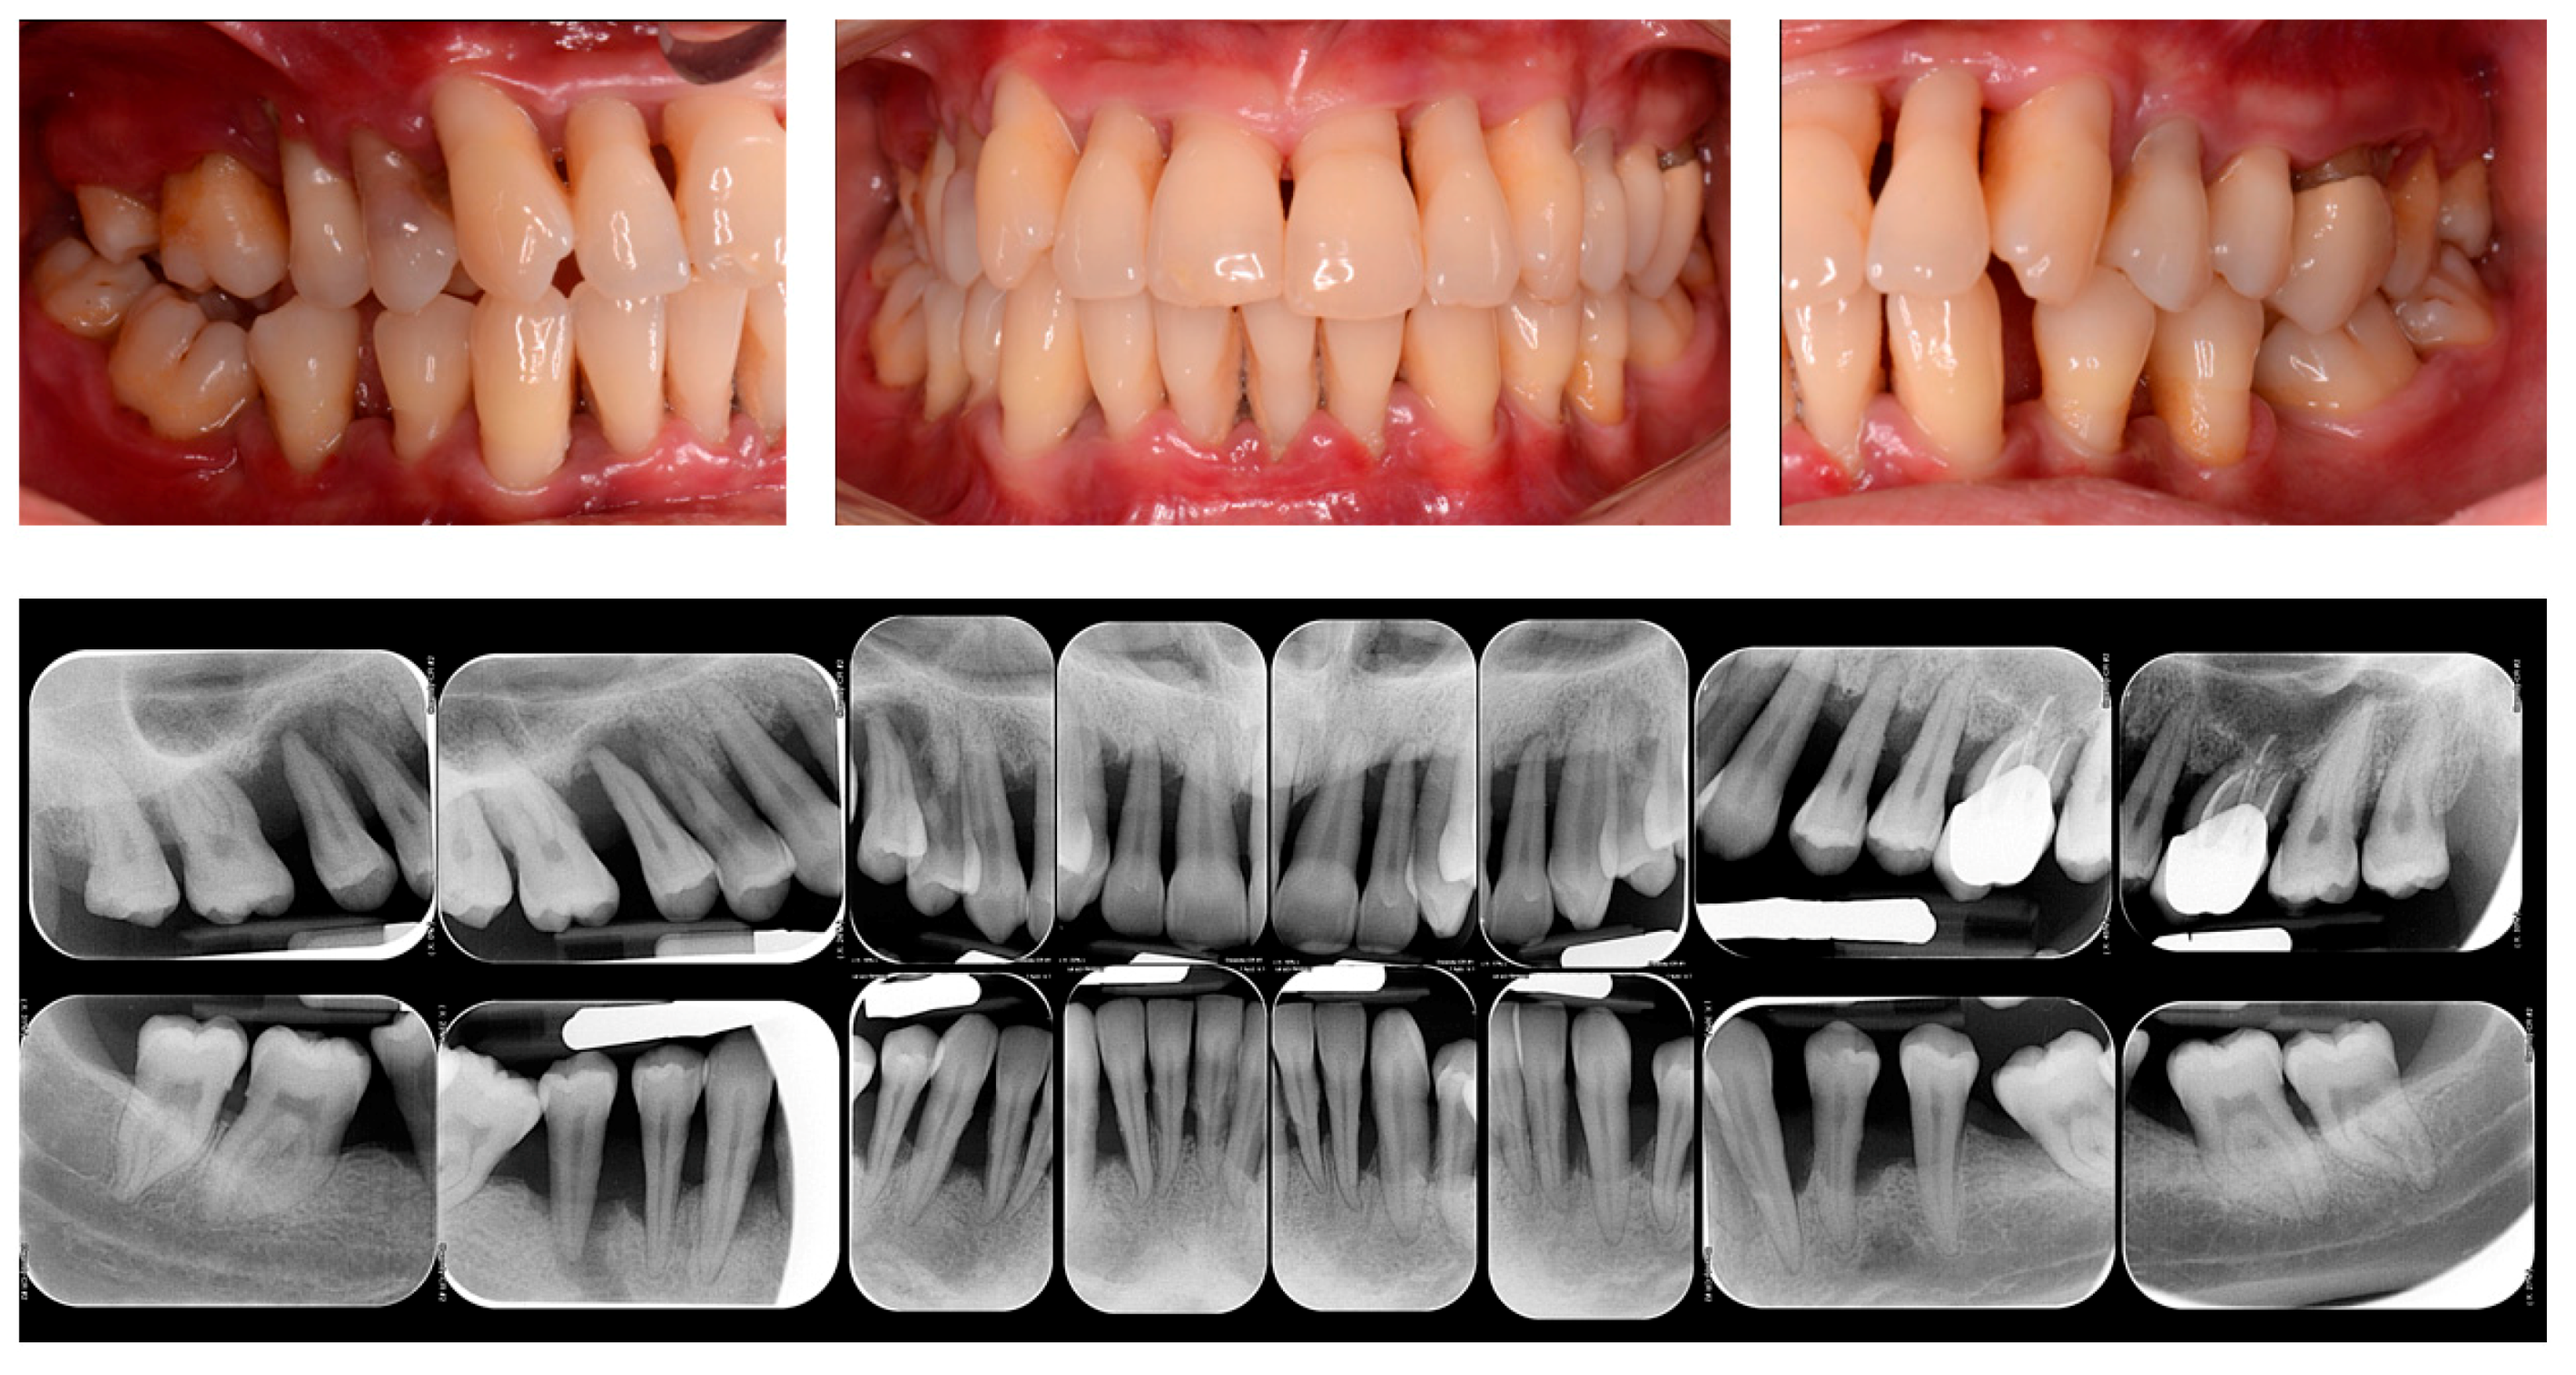

The success of periodontitis therapy, both in the short- and long term, depends on the effect of physical disintegration of the supra and subgingival periodontal pathogens presented in the biofilm [24]. The initial causal therapy mainly consisted of oral hygiene instruction and professional scaling and root planing (SRP). Both the supra- and subgingival pathogens and calculus are mechanically disrupted, with combined and synergic effects induced by periodontal debridement and domiciliary oral hygiene instructions [25]. In this regard, the gold standard of non-surgical therapy of periodontitis is represented by the SRP performed by both hand and ultrasonic instruments alone, with a demonstrated microbial and clinical effectiveness in the short-term period [26,27] (Figure 1).

Figure 1.

Clinical and Rx images of a patient with periodontitis.

It has been previously shown that the mechanical disruption of supra- and subgingival biofilm by the non-surgical periodontal therapy performed by SRP alone can reduce the plaque index (PI) and the bleeding on probing (BOP) in around 45% of periodontal sites [28]. On this regard, following non-surgical periodontal therapy, a reduction in the probing depth (PD) has been demonstrated in a range of 1.29 mm for periodontal pockets with an initial PD of 3–4 mm and of 2.2 mm for the pockets ranged 5–6 mm and an improvement in the clinical attachment level (CAL) in a range of 0.5–2 mm [29,30].